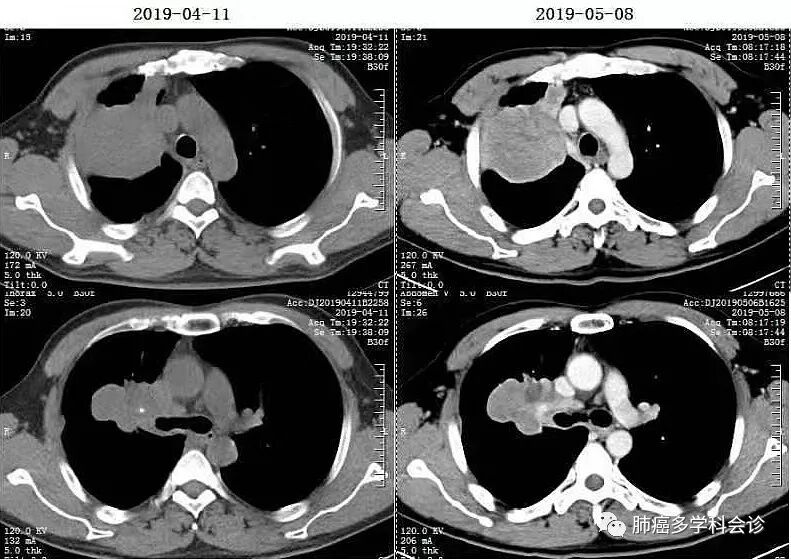

2018.10.28 - 2019.03.22,在呼吸科接受一线化疗:“吉西他滨+奈达铂”× 6周期,最佳疗效PR。2019-04-11复查CT,示疾病进展:

- 【多学科会诊病例】 以下为一位肺鳞癌患者经过二个方案化疗后,疾病进展、不耐受继续化疗。三线“PD-1抗体+安罗替尼”治疗, 2周期后肿瘤明显缩小: 患者郑WD,男,46岁,吸烟20余年,平均20支/